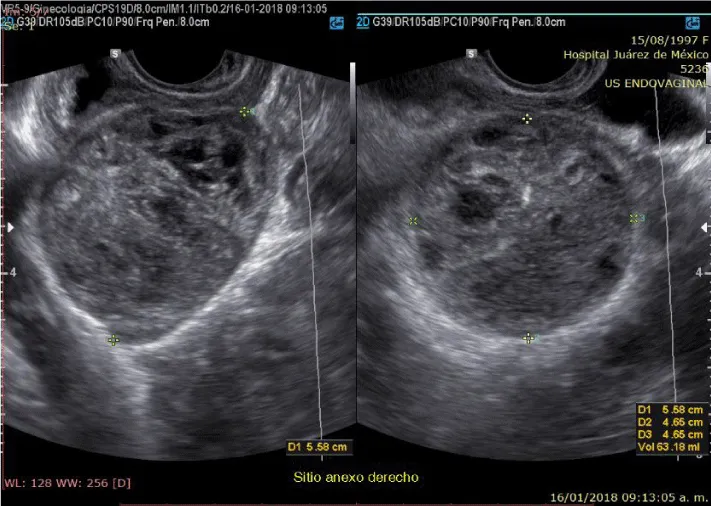

A 20-year-old married woman, with no history of pregnancy, who was admitted to the hospital for colicky abdominal pain in the right iliac fossa with radiation to the right iliac fossa from moderate to severe with Visual Analogue Scale with nausea and vomiting treated with analgesics presenting slight improvement; It is requested, quantification of the beta fraction of gonadotropin with figures of 112,337 mIU/mL and pelvic ultrasound with a report of a complex cyst of the right ovary without evidence of free fluid in the cul-de-sac; in relation to probable dysgerminoma or tumor of etiology to be determined; the hematic biometry with hemoglobin of 15.8 and hematocrit of 45, platelets of 313,000, leukocytes of 11,300 and 2 bands; reason for which she is referred to Hospital Juárez de México and once hospitalized; on August 18, 2017; she presents low-cost symptoms; and the studies are repeated quantification of beta fraction of Human Chorionic Gonadotropin (hGC) greater than 5,000, hemoglobin of 18 grams, hematocrit of 47%, leukocytes of 12,000, platelets of 367,000, lactic dehydrogenase of 473, direct bilirubin of 0.8 and the 2.3 total; normal liver transaminases; Ultrasound reports uterus in anteversion of 79x26x31mm, homogeneous myometrium, endometrial thickness of 7.9mm and right annex with lesion of 114 x83x79mm and total volume of 394cc, heterogeneous with linear images in its interior punctiform, the ultrasound diagnosis was, probable right annex teratoma tumor cystic.

On physical examination, the patient with generalized pallor of the skin and integuments, hypotensive, tachycardic, diaphoretic, without cardiorespiratory compromise, globose abdomen due to abundant adipose panniculus, perstalsis present, pain on palpation in the right iliac fossa on bimanual touch, the uterus is delimited 8x5 cm, right annex, 12x9 cm adnexal tumor, irregular, firm, pain on cervical mobilization, with spotting-shaped transvaginal hemorrhage, extremities without edema, normal tendon reflexes. According to the clinical presentation, imaging studies, on suspicion of ruling out ectopic pregnancy, an exploratory laparotomy was performed, with findings of the right annex of 20x15 cm adhered to the uterus and sigmoid rectum without evidence of hemoperitoneum and a right salpingo-oophorectomy was performed for probable right ectopic pregnancy with hematic loss due to the surgical procedure of 40cc and sent to pathology for definitive histopathological study, during follow-up a control gonadotropin quantification was requested with the last report of 1 103 918.7 mUI/mL. The histopathological results of the macroscopic surgical specimen were right salpingo-oophorectomy, with choriocarcinoma with extensive necrosis, 1 cm tumor extension to the ovarian surface not identified, lymphovascular invasion present and free surgical margins of the residual ovarian tumor with cystic follicles, Figure 1 and the report microscopic, Figures 2-4. A new hCG quantification is performed, negative head tomography and chest tomography with probable metastasis due to pulmonary nodule, in abdomen and pelvis, presence of peritoneal carcinomatosis, with free fluid and lumbar puncture reports negative for malignant cells and chemotherapy based on cisplatin and etoposide 5 sessions and the patient is disease-free after two years of follow-up.